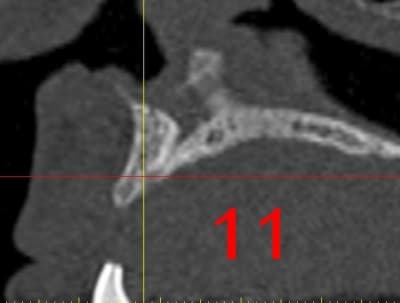

La première diapo est un essai pour justifier le concept (os non destiné à une utilisation greffe)

la deuxième est "tapée" dans une tête de femur de mauvais qualité (rejetée)

la troisième et suivante ce sont "les greffons" définitifs.

La précision 3D du scan est elle suffisante pour une adaptation passive sur l'os réel ?

La tu nous montres sur un stereolitique obtenu à partir du scan, ok ça colle mais en bouche ?

concept très prometteur. on obtient effectivement un contact intime du greffon avec le site receveur.